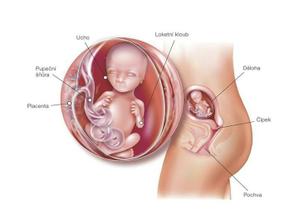

Jak asi víte, těhotenství je členěné na tři časové úseky, kterým říkáme trimestry – každý z nich trvá tři měsíce. Každý z trimestrů je zcela specifický, probíhají v něm určité charakteristické změny, podstupuje se vyšetření a nesou s sebou jiné pocity a obavy nastávající maminky.

- I. trimestr = 1. - 12. týden těhotenství

- II. trimestr = 13. - 28. týden těhotenství

- III. trimestr = 29. - 40. týden těhotenství